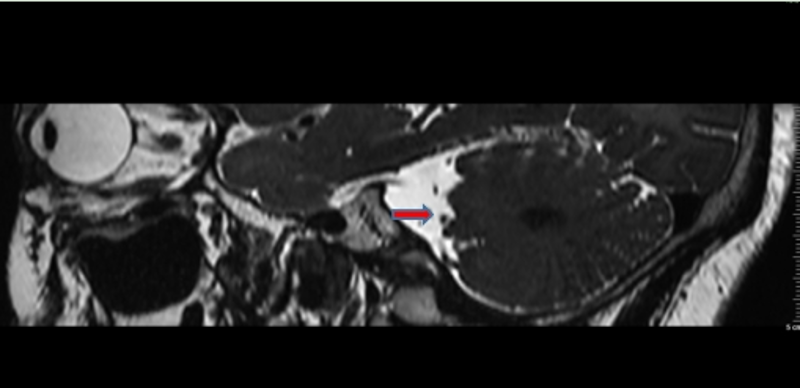

马阿姨在完善头部 MRI神经血管检查后发现舌咽神经与相邻的小脑后下动脉紧贴,结合症状,舌咽神经痛为血管压迫所致,具备手术指征。在马阿姨及其家属的强烈要求下,经苑玉清主任医师手术组讨论后为马阿姨进行手术治疗。

图一:术前头部MRI神经血管成像(舌咽神经与相邻血管紧贴)